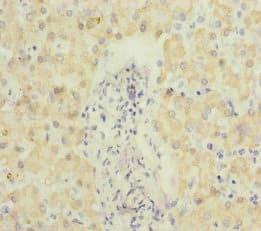

Echs1 Antibody Ab235835  Immunohistochemistry Formalin Pfa Fixed Paraffin Embedded Sections Img59629